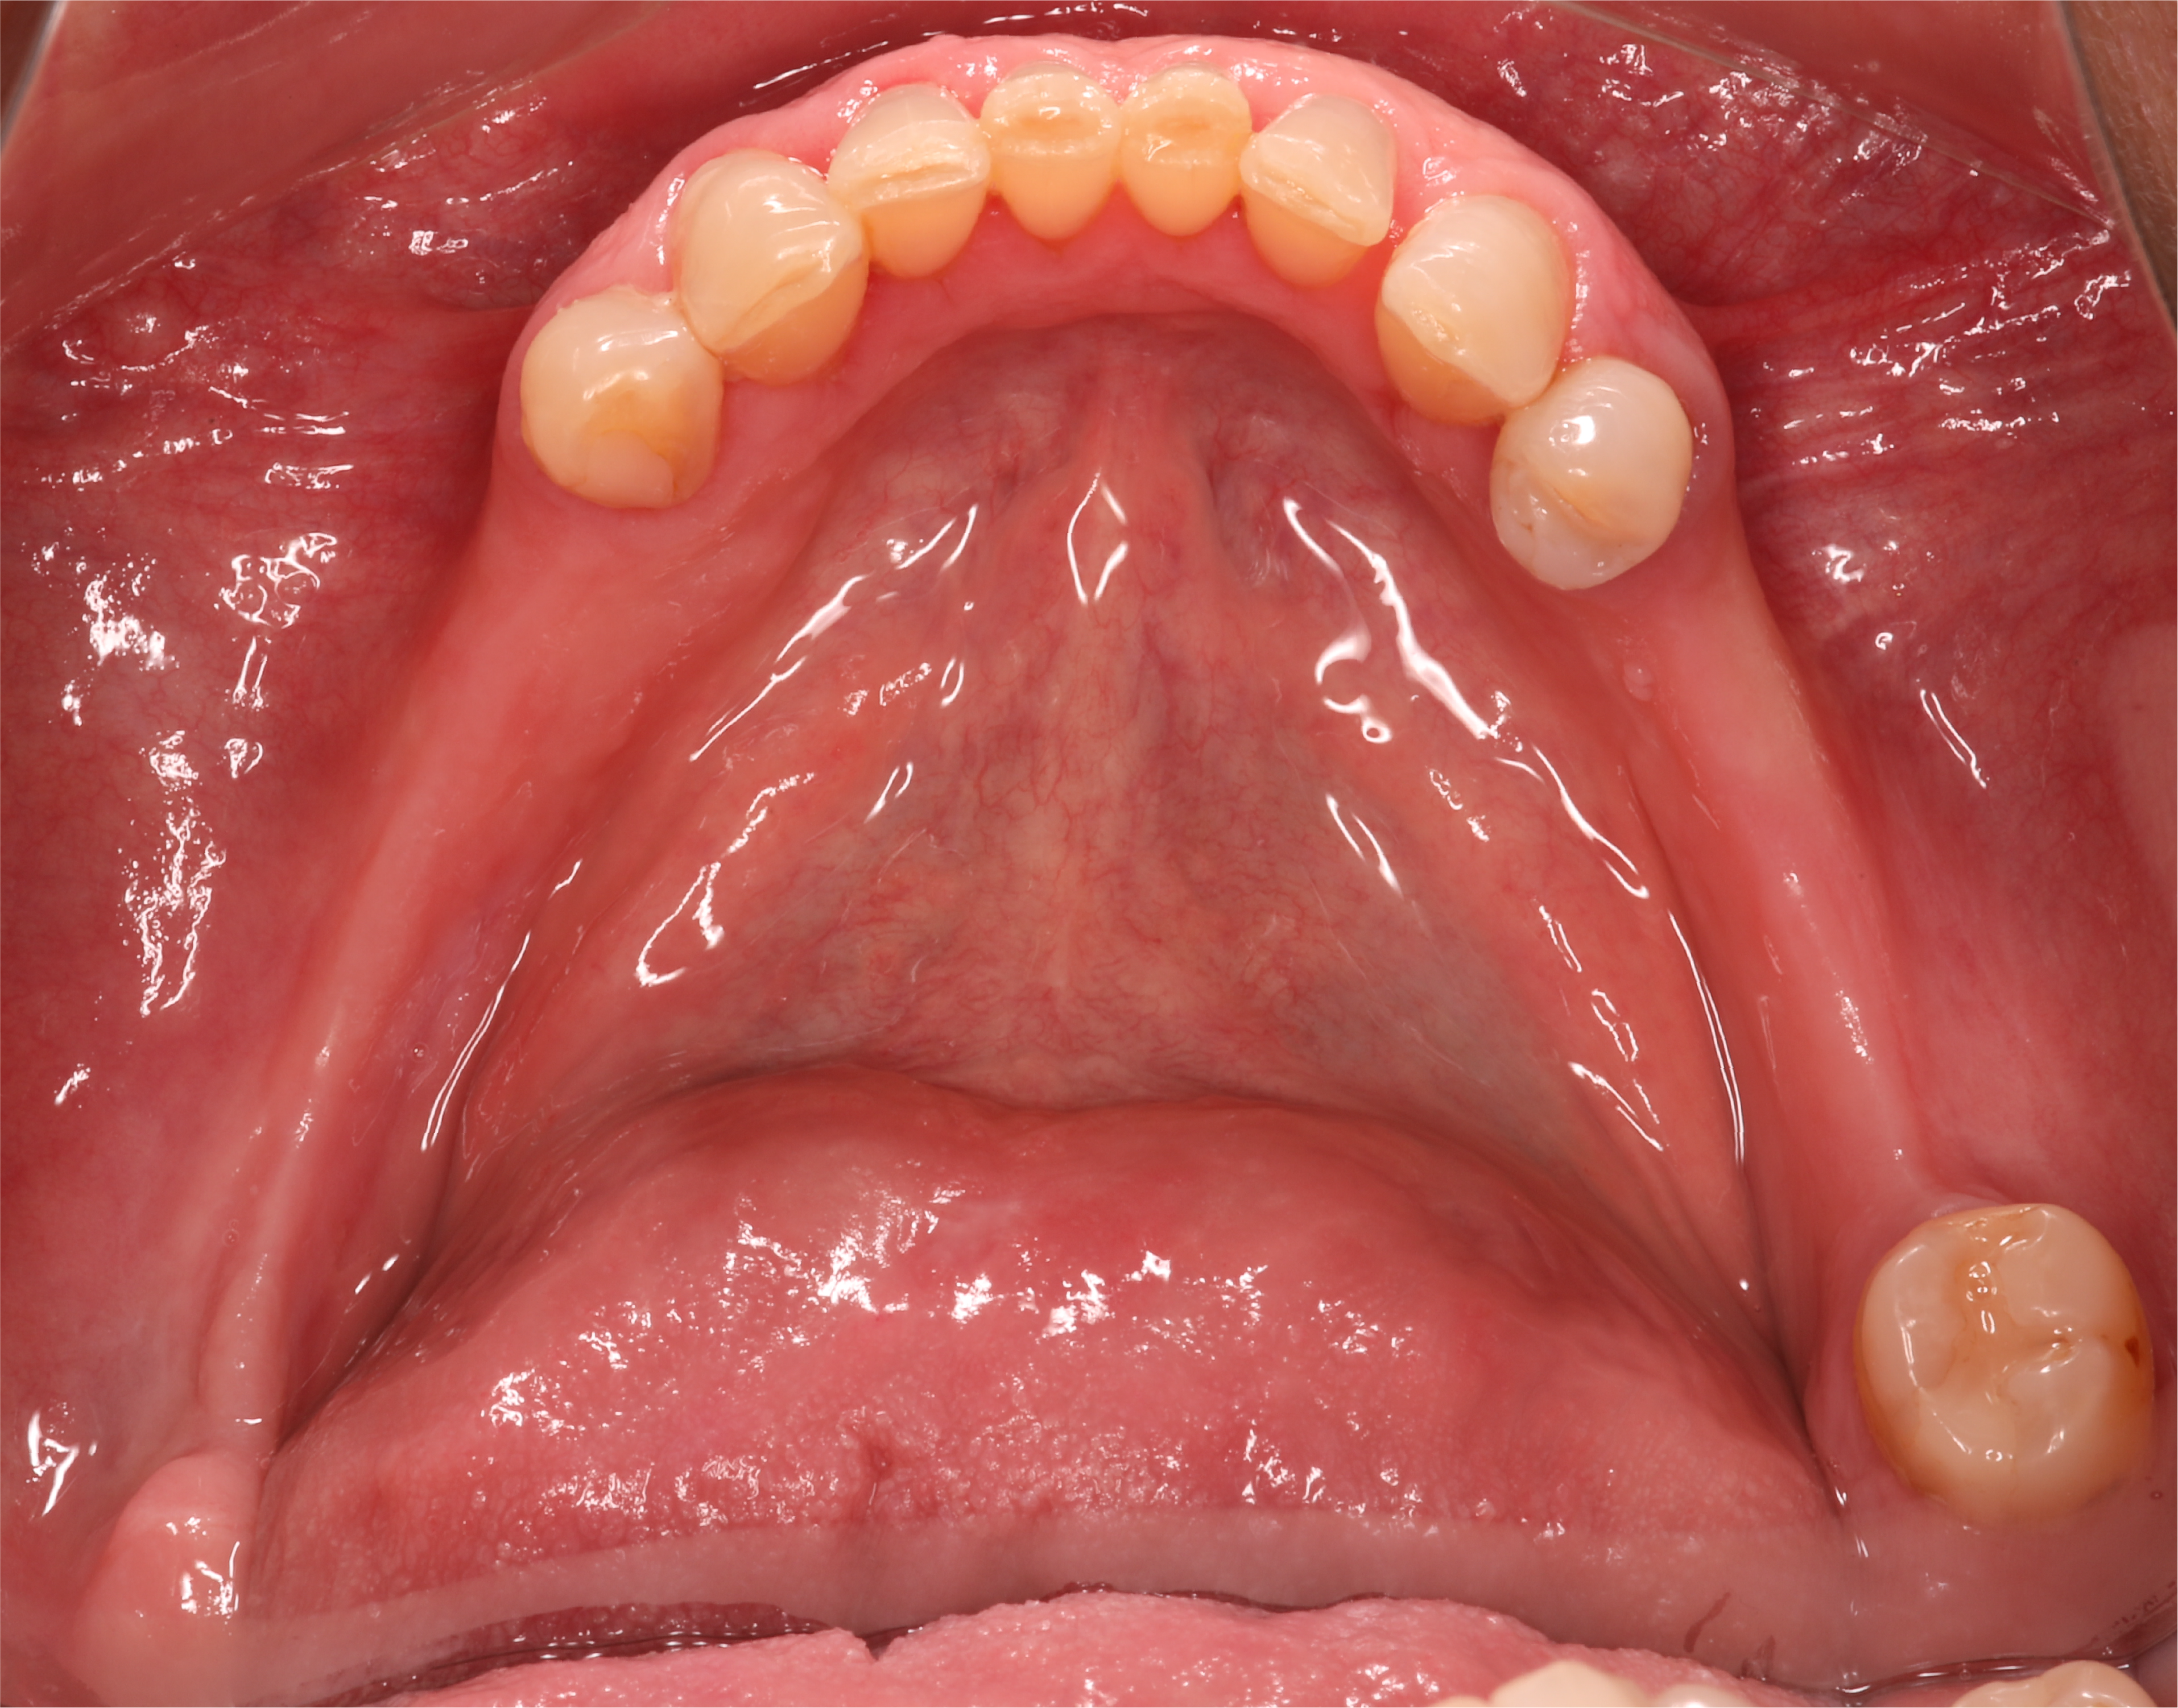

Trabalho final inserido.